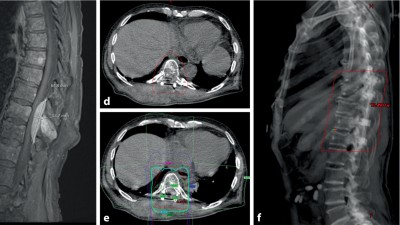

Die Mehrzahl der Personen mit multiplem Myelom benötigt während ihres Krankheitsverlaufs eine lokale Therapie. Diese kann aufgrund von Schmerzen, (drohender) Instabilität oder neurologischer Symptomatik notwendig sein. Dabei kommen insbesondere eine Radiotherapie, operative Eingriffe oder eine Kombination der beiden Methoden zum Einsatz.

Ein 48-jähriger Patient berichtet von belastungsabhängigen Schmerzen in den Beinen seit mittlerweile zehn Jahren. Bildgebende Untersuchungen der Hals- und Lendenwirbelsäule konnten die claudicatioartigen Beschwerden bislang nicht erklären. Eine lange überfällige MRT des Thorakalbereichs führt schließlich zur richtigen Diagnose.

Chilaiditi-Syndrom in einer CT-Aufnahme/© Peters F & Ritz J-P/ all rights reserved Springer Medizin Verlag GmbH, Initial potenziell instabile Läsion von BWK 10 bei Multiplem Myelom/© Kaufmann, J., Schmidberger, H. / all rights reserved Springer Medizin Verlag GmbH, Springer Medizin Podcast - Endometriose/© (M) Willer D. et al. / all rights reserved Springer Medizin Verlag GmbH Logo: Springer Medizin Verlag GmbH, Zentrale Lungenembolie/© Springer Verlag Berlin Heidelberg 2015, Volumetrie des Bulbus olfactorius/© Keweloh S.. et al. doi.org/10.1007/s00106-025-01650-z unter CC-BY 4.0, Gebrochener Fuß im Gips/© Aleksandr Kirillov / stock.adobe.com (Symbolbild mit Fotomodell), CT-Pulmonalisangiographie/© Das M et al. doi.org/10.1007/s00117-016-0100-3 unter CC-BY 4.0, Kanüle für Katheterbehandlung/© romaset / stock.adobe.com, Komplexe, offene Fraktur des Ellenbogens vom Grad 2/© Springer Medizin Verlag GmbH, Mann erhält einen CT-Scan /© Mark Kostich / stock.adobe.com (Symbolbild mit Fotomodell), Verschlussazoospermie bei unilateraler zystischer Alteration der Samenblase und kontralateraler Samenblasenagenesie/© Wittler C et al, Indikationen zur konventionellen Bildgebung am Ellenbogen/© Rentschler V et al. / all rights reserved Springer Medizin Verlag GmbH, Person schenkt Bier in Kolben/© Parilov / Stock.adobe.com (Symbolbild mit Fotomodell), Neoadjuvanten Strahlentherapie bei Liposarkom/© Podleska, L.E. et al. / all rights reserved Springer Medizin Verlag GmbH, Frau erhält eine Strahlentherapie/© Mark Kostich / stock.adobe.com (Symbolbild mit Fotomodell), Schaumiges Bronchialsekret bei akutem Lungenödem/© Eichner M. doi.org/10.1007/s00063-025-01258-9 unter CC-BY 4.0, Bildgebung bei akuter Organblutung/© Nadjiri J / all rights reserved Springer Medizin Verlag GmbH, Bildgebung bei Beckenfraktur mit Blutung der A. iliaca interna/© Fink CB et al. / all rights reserved Springer Medizin Verlag GmbH, Traumatische Aortenverletzung/© Maier J et al. / all rights reserved Springer Medizin Verlag GmbH, Oberbauchsonoraphie/© C. Raschka, Muzinöses Prostatakarzinom/© Garzaro JRR et al. / all rights reserved Springer Medizin Verlag GmbH, Intraspinales thorakales Lipom/© Andreas Frank / all rights reserved Springer Medizin Verlag GmbH, Frau bei Strahlentherapie/© (M) Mark Kostich / Stock.adobe.com (Symbolbild mit Fotomodellen), Search Icon, Frau hält sich eine Brustseite nach Mastektomie/© chotiga / Stock.adobe.com (Symbolbild mit Fotomodell), Radiologin richtet Mammographiescreening ein/© LIGHTFIELD STUDIOS / stock.adobe.com (Symbolbild mit Fotomodellen)